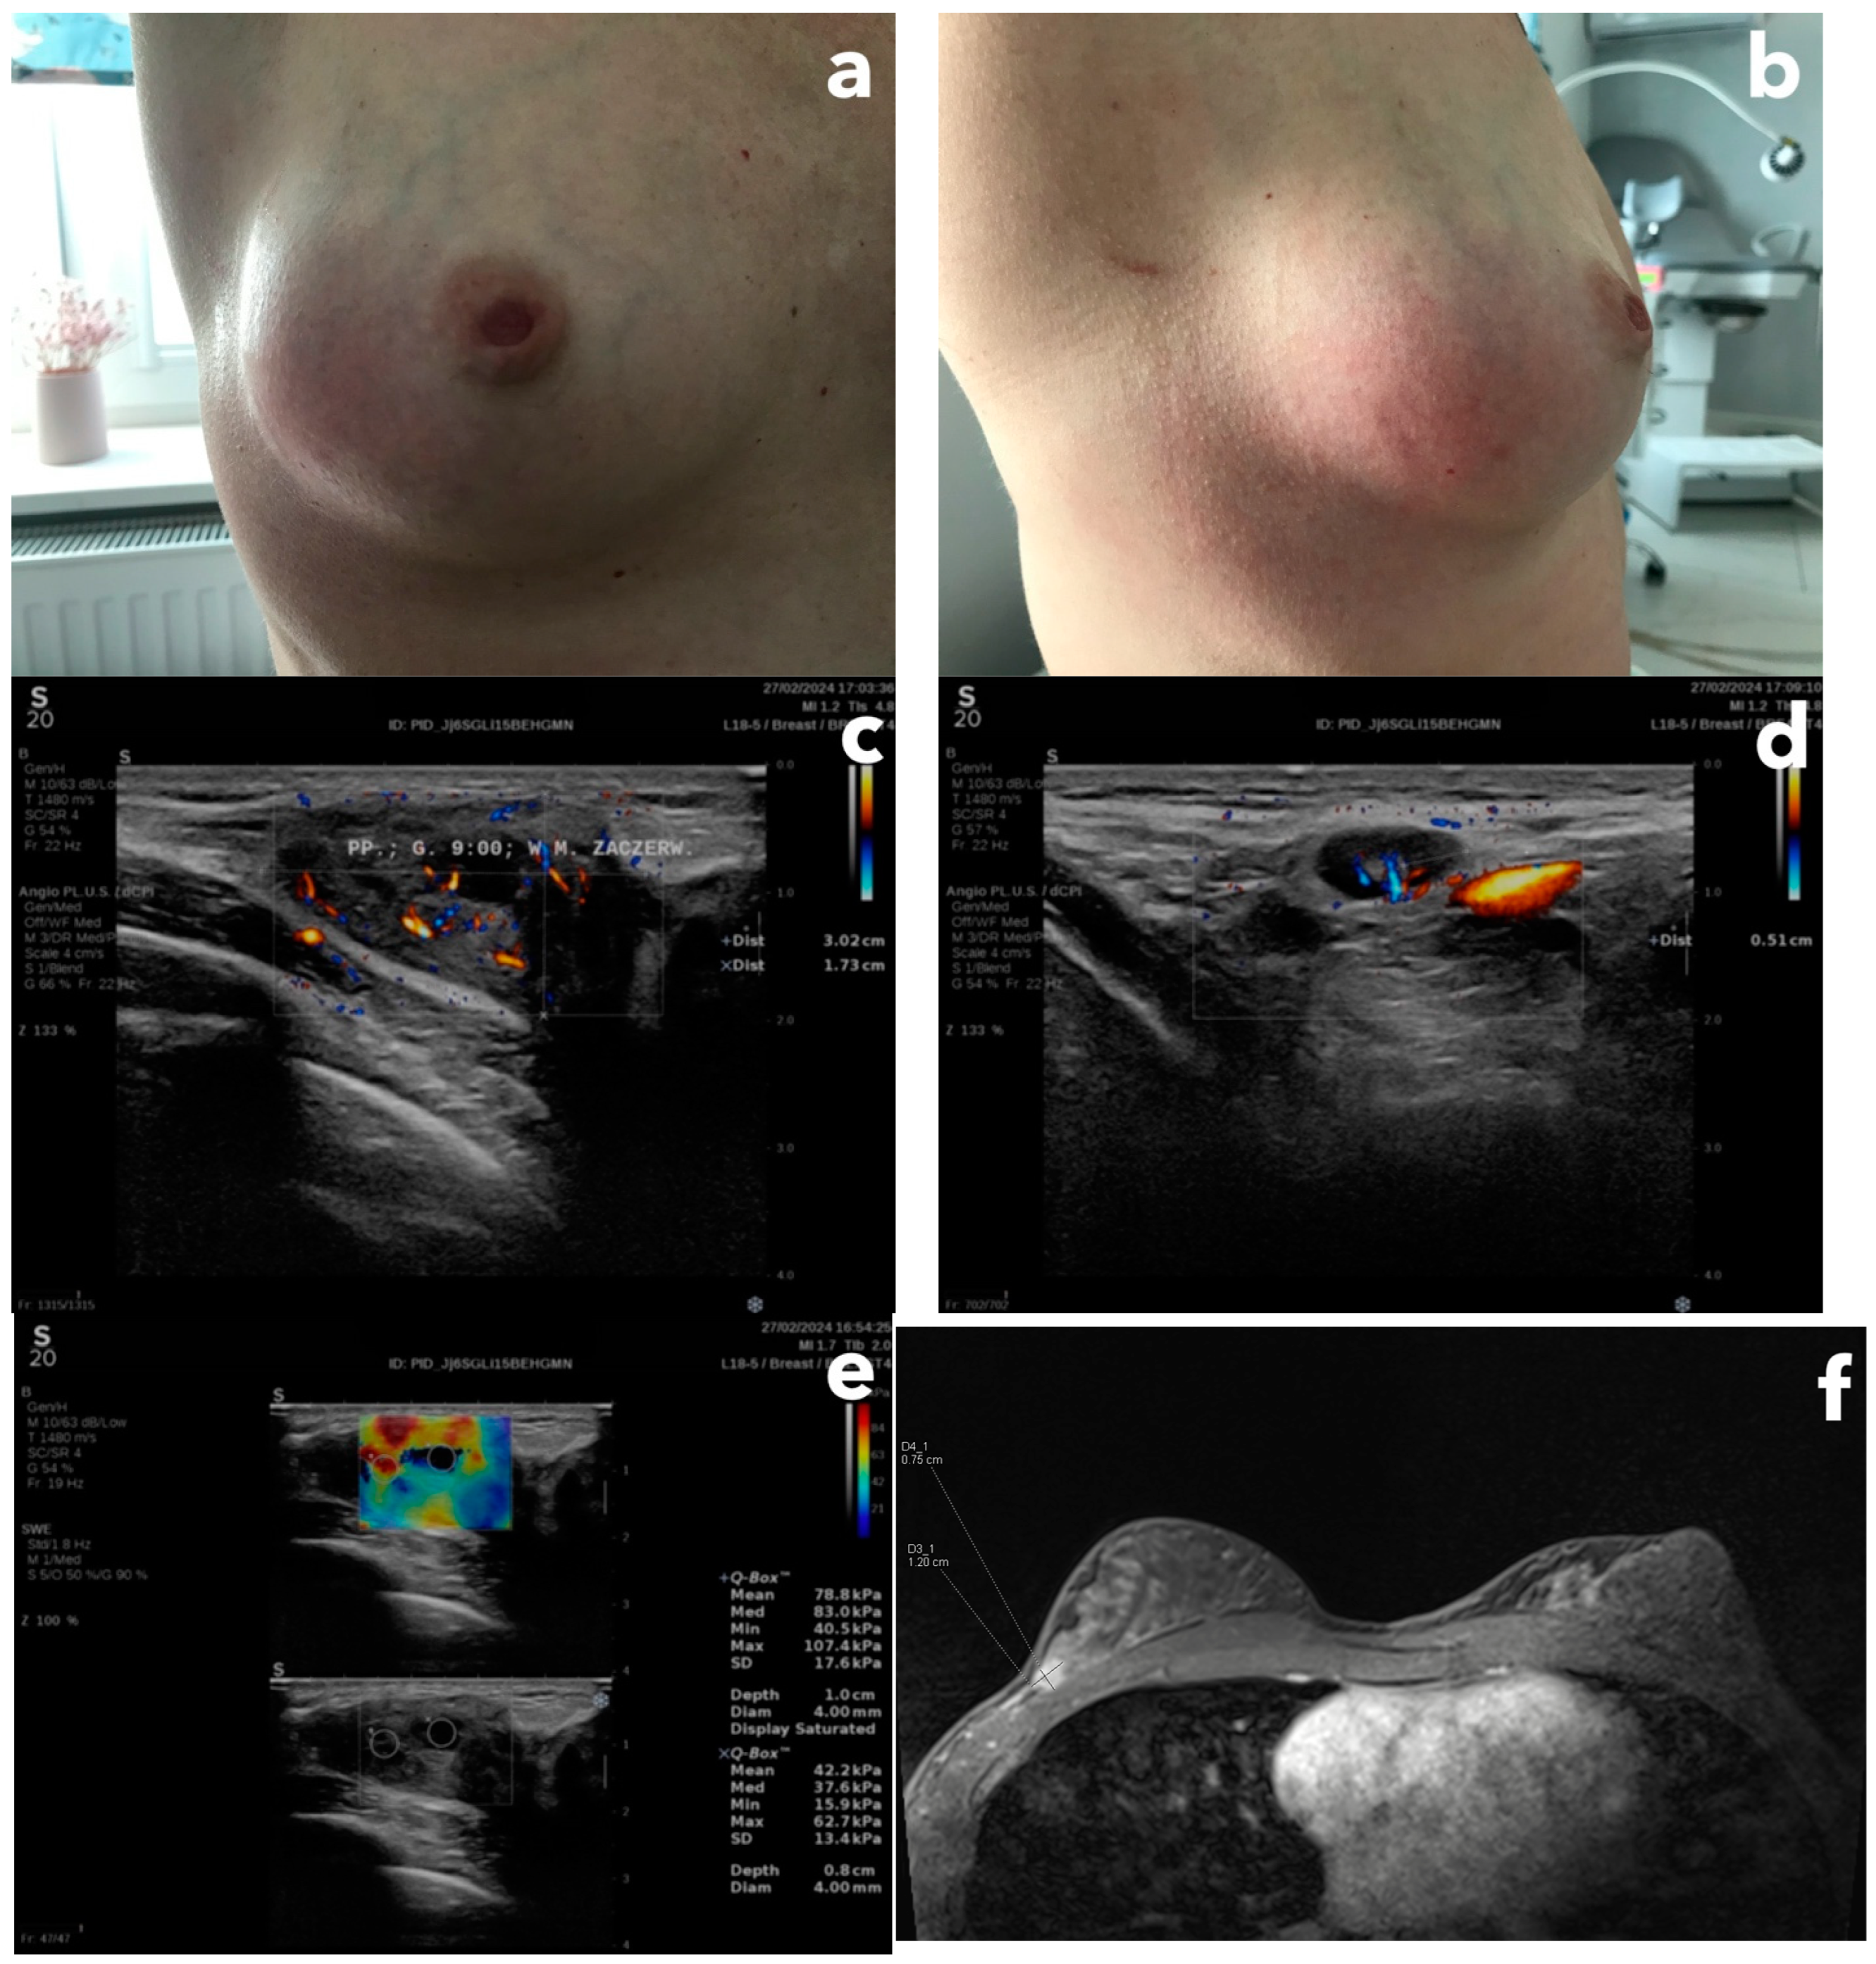

A 44-year-old female patient, came to a senologist (breast specialist) for a consultation after she remarked a swelling, redness, and lump in the upper, outer quadrant of her right breast (Figure 4a,b). She had never been pregnant, she had a history of breast cysts, and her family history of cancer was negative. The patient is a physiotherapist by profession and denied breast injury. She was first referred to her family doctor, who, after examining her breasts, scared her that she had cancer and immediately referred her to a breast cancer unit. However, the patient wanted to verify it as soon as possible and made a private office appointment with a senologist.

On palpation, there was an isolated resistance of approximately 5 cm in size and it was tender. The retracted nipples were on both sides. The senologist, after performing a breast ultrasound examination, categorized the lesion as BI-RADS-4b (Figure 4c–e), and ordered a biopsy, but after performing an MRI examination due to the dense, glandular structure of the breasts (Figure 4f).

The histopathology showed, after considering the clinical and radiological picture, the presence of immature fibrous tissue with resorption and reparative changes after previous damage, in the form of sparse resorptive histiocytic granulations and cholesterol remnants. The ducts and lobules were changed reactively. The diagnosis concluded was a consequence of trauma or damage to the cyst wall. The histopathological picture is consistent with the diagnosis of idiopathic granulomatous mastitis. This inflammation typically affects women aged 20–40, pregnancy is a risk factor, in 20% of cases the inflammation is bilateral, and in half of the cases, it clinically resembles inflammatory cancer. In ultrasound, it usually presents an area of hypoechoic foci up to 80 mm [26].

The cause of these clinical symptoms was most likely an injury unnoticed by the patient (perhaps during her physiotherapeutic work). Nine months after that event, the patient did not report any complaints.

Figure 4. (panel). (a) Front view at the right breast with its distortion, swelling, and redness of the skin, (b) Lateral view at the right breast, (c) B-mode ultrasound image with microflow presentation, corresponding to the redness location, BI-RADS-4b, (d) a suspected axillary lymph node with enlarged cortex, (e) shear-wave elastography presentation of the lesion showing the increased stiffness (mean stiffness value equals 78.8 Kilopascals) (f) T1-weighted MRI image showing rapid contrast enhancement with diffusion restriction of the lesion localized at 7/8 h, subcutaneously, and in adherence to the fascia of the pectoralis major muscle.